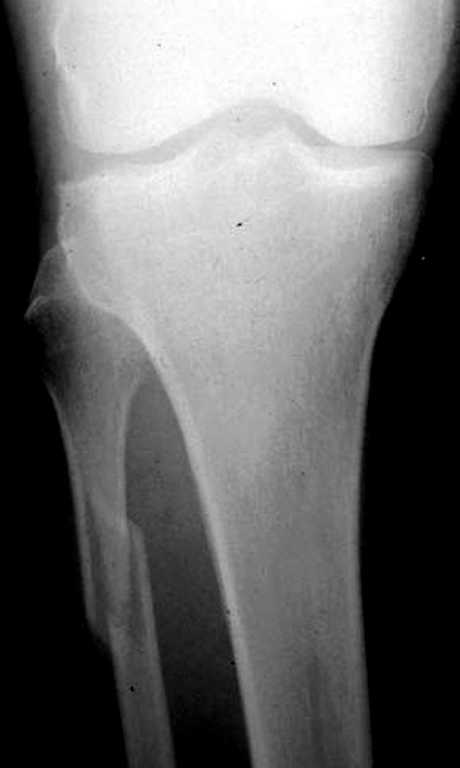

Перелом малоберцовой кости есть, понятно. Но боли в голеностопном суставе! А как вы изучали патологическую подвижность стопы? Есть стрессовые снимки?

Вопрос, который возникает у меня при виде таких снимков,- "Какой механизм травмы?"

Если это прямой удар, то кроме перелома м,б кости и ушиба мягких тканей ничего нет.

Если механизм непрямой, т.е. подворачивание (ротация) стопы, то это повреждение надо классифицировать как нестабильный перелом лодыжек (44 С.2) с повреждением синдесмозных связок.... Да, на обычных рентгенограммах можно

видеть идеальный голеностопный сустав

Проблема здесь не в переломе м/берцовой кости.

У больной есть боли в г/стопном суставе, возможно механизм травмы не прямой, тогда данное повреждение надо рассценивать как надсиндесмозное повреждение м\берцовой кости, пусть и такое высокое при Дюпиетреновском механизме травмы.

Поэтому :

1. при изолированном переломе м/берцовой кости не оперировать, иммобилизация не нужна, консолидация через 3 недели на Р- граммах можен быть

и не видна